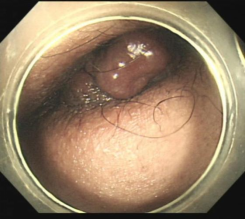

内痔硬化治疗,微创,无痛苦,迅速解决肛周不适、便后内痔出血问题,术后短期内可回复正常生活。

混合痔,术前便血和痔疮脱出肛门口,行内痔套扎治疗,解决了出血和痔疮脱出问题。

内痔的硬化和套扎治疗